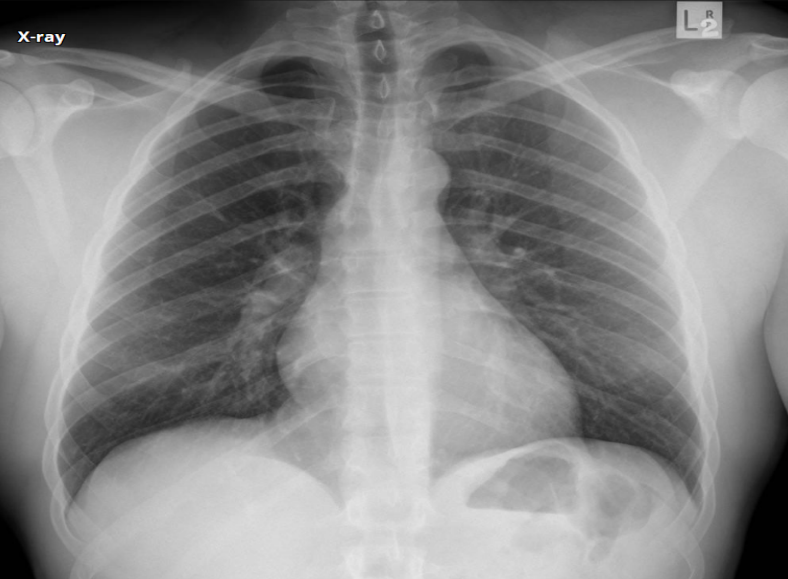

What view

PA (lower diapjragm, full lungs/large, horizontally oriented clavicales, scapula not displaced)

AP (higher diapjragm, smaller lungs, obliquely oriented clavicales, scapula displaced, falsely enlarged heart and medastinum)